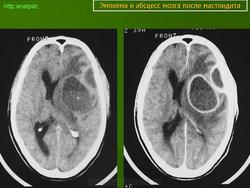

Абсцесс головного мозга – это очаговое скопление гноя в мозговом веществе, окруженное капсулой.

Возникают посттраматические абсцессы при проникающих ранениях, а также при закрытой травме. В последнем случае инфицирование происходит через кровь из отдаленного очага инфекции. Основными возбудителями являются стафилококки, стрептококки, реже грамотрицательная флора, нередко наблюдается сочетание нескольких возбудителей.

Компьютерная (КТ) или магнитно-резонансная (МРТ) томография головного мозга являются ведущими методами диагностики посттравматических абсцессов, позволяющих судить об их расположении, объеме, структуре, консистенции, содержимом, воздействии на вещество головного мозга. Для исключения опухолей головного мозга, туберкулом, паразитарных заболеваний проводится ОФЭКТ (однофотонная эмиссионная компьютерная томография).